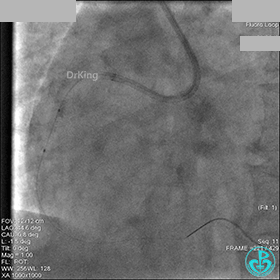

1周后再次上台,右冠脉3级血流,3段局限性严重狭窄,内膜模糊,应该是上次操作夹层遗留下的血肿。

先处理前降支开口严重狭窄并顺利植入前降支到左主干支架。